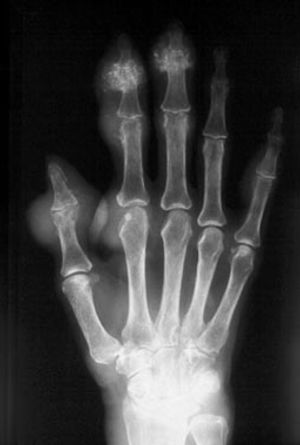

Image IQ Quiz: Patient Presents with Swollen JointsByM. Mohammed, M.D.April 1st 2021What is your diagnosis from this hand X-ray?